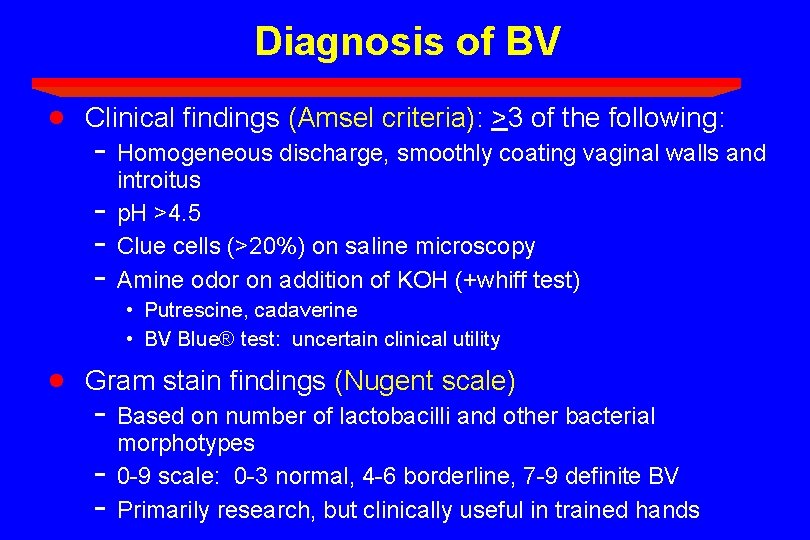

Diagnosis of BV · Clinical findings (Amsel criteria): >3 of the following: - Homogeneous discharge, smoothly coating vaginal walls and - introitus p. H >4. 5 Clue cells (>20%) on saline microscopy Amine odor on addition of KOH (+whiff test) • Putrescine, cadaverine • BV Blue® test: uncertain clinical utility · Gram stain findings (Nugent scale) - Based on number of lactobacilli and other bacterial - morphotypes 0 -9 scale: 0 -3 normal, 4 -6 borderline, 7 -9 definite BV Primarily research, but clinically useful in trained hands